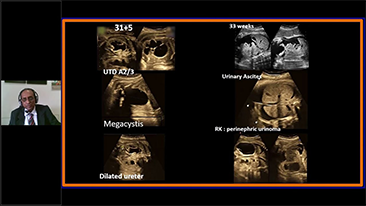

Using ultrasound as part of an optimised OBG workflow can support large patient volumes for women's health screening. For example, central nervous system (CNS) malformations are one of the most common congenital abnormalities. Due to imaging conditions such as poor fetal position, the median sagittal plane (MSP) is particularly difficult to obtain from 2D ultrasound. Therefore, automated detection and measurements can greatly enhance scanning efficiency.